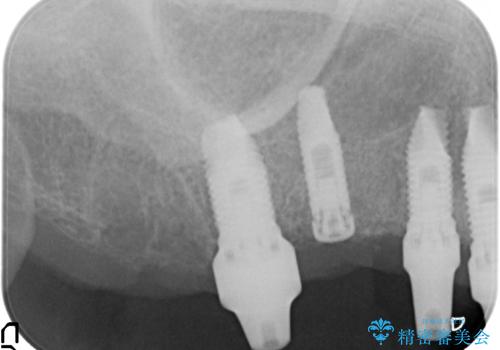

- 他院で1本インプラントを入れたまま治療に通うことができなくなり、途中からの治療を希望され来院されました。

既に埋入されているインプラントは位置が悪いのでそのまま骨内に留置することとし、新たに咬合機能を回復すべく3本のインプラントを埋入すると同時に吸収した骨幅を増やし、安定してインプラントで噛める環境整備を目指します。

- 120万円(インプラント×3 チタンカスタムアバットメント×3 メタルボンドクラウン×3 骨造成 歯肉移植)費用は治療当時の料金となります

インプラントが長持ちするために、インプラント周囲の十分な骨量・角化歯肉の存在・安定した咬合を一つづつ整備する治療を行いました。